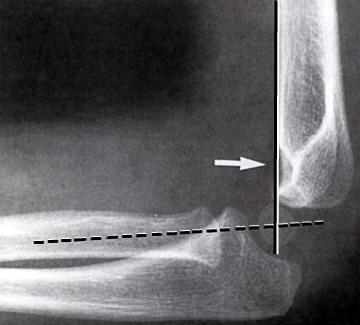

Dislokation: En linie langs forsiden af humerus går normalt igennem midterste

1/3 del af capitulum humeri. Hvis hele capitulum ligger bagved denne linje skal

der reponeres og osteosynteres i GA. Hos børn under 4 år tillades lidt større